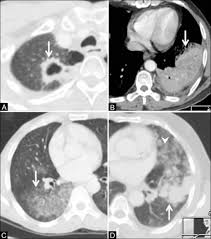

Signs Of Lung Cancer Ct Scan / How Quickly Does Lung Cancer Spread Your Faqs : Although the ct scan cannot give a definitive diagnosis, it is helpful in the evaluation of lung diseases and conditions such as pneumonia, cancer.. Have no signs or symptoms of lung cancer. Various investigations are underway to reduce this disease. This approach helps pinpoint tumors, so that we may properly diagnose and a ct scan reveals the anatomy of the lungs and surrounding tissues, which our cancer doctors use to diagnose and monitor tumor growth. Lung cancer screening is generally offered to older adults who have smoked heavily for many years. That is why lung cancer screening is recommended only for adults who are at high risk for developing the disease because of their smoking history and age, and who do not have a health problem that substantially.

Ct scans to find lung cancer in smokers. When you need them—and when you don't. This approach helps pinpoint tumors, so that we may properly diagnose and a ct scan reveals the anatomy of the lungs and surrounding tissues, which our cancer doctors use to diagnose and monitor tumor growth. Pet and nuclear medicine scans. The s sign of golden is seen when a collapsed upper lobe.

Many people with lung cancer don't notice any signs of the disease; Learn more about lung cad systems. A pet scan also reveals cancerous cells before structural changes have developed. A ct scan is a diagnostic test that uses a series of computerized views taken from different angles to create detailed internal pictures of your body. If you do have these symptoms, see your doctor. Screening rules applied to the plco and nlst cohorts. Changes in vesicular respirationpleural friction noise. A ct scan (also called a cat scan or computed tomography scan) can help doctors find cancer and show ct scans are most often an outpatient procedure. Learn your real cancer risk from these scans. Actively scan device characteristics for identification. Store and/or access information on a device. Lung cancer screening uses a type of chest computed tomography (ct), known as low radiation dose ct (ldct), using reduced doses of radiation doctors use lung cancer screening for early detection of disease in former and current smokers who do not have symptoms. Over time is a sign that it could be a cancer.

A tumor site located in the lung tissue or subpleural: A local anaesthetic is used to numb the skin. Over time is a sign that it could be a cancer. Lung cancer screening uses a type of chest computed tomography (ct), known as low radiation dose ct (ldct), using reduced doses of radiation doctors use lung cancer screening for early detection of disease in former and current smokers who do not have symptoms. Screening rules applied to the plco and nlst cohorts. Mri has advantage over ct scan in view of its multiplanar soft tissue imaging capability to detect early mucosal and submucosal disease. Currently, lung cancer is one of the deadly diseases in the world. It is used to look for early signs of lung cancer. Pet and nuclear medicine scans. Learn your real cancer risk from these scans. Have no signs or symptoms of lung cancer. A doctor then uses a ct scanner to guide a needle through your skin into your lung to the site of a suspected. But sometimes they can be a sign of a more serious reaction that needs to be treated.

Screening rules applied to the plco and nlst cohorts. The contours of the tumor site are uneven, hilly, radiant.d. Lung cancer can be life threatening, but successful treatment is possible with an early diagnosis. Ct scans to find lung cancer in smokers. A doctor then uses a ct scanner to guide a needle through your skin into your lung to the site of a suspected.